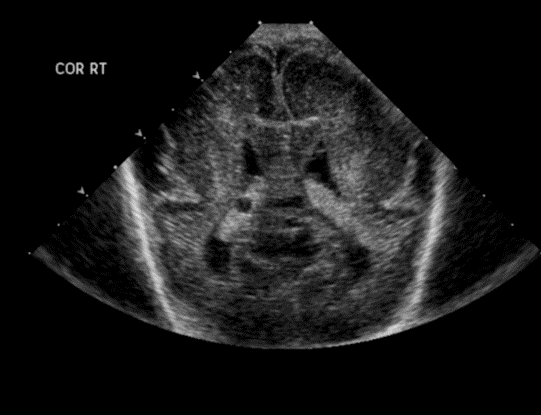

Info Images Findings Impression Reco/Acuity Case Images View Images / Launch Visage Case Notes History Full term infant. We are asked to evaluate posterior fossa cyst. Exam Gray scale and Doppler Ultrasonographic examination of the head. Prior Study N/A Dicom View Reference Material

Section 1 Submit Findings Case149 Findings Brain The brain is immature. Yes No There is under-sulcation and open sylvian fissures. Yes No There is/are multiple hypoechoic areas in the periventricular white matter. Yes No There is/are multiple hyperechoic areas in the periventricular white matter. Yes No There is diffuse cerebral edema with diffusely increased echogenicity of the brain parenchyma and loss of grey white matter differentiation. Yes No The thalami/basal ganglia are hypoechoic. Yes No There is periventricular calcification. Yes No There is intra-parenchymal calcification. Yes No CSF spaces/ventricular system There is a prominence of the extra axial fluid spaces. Yes No There are debris/septations in the extra axial fluid spaces. Yes No There are debris/septations in the ventricles. Yes No There is a subdural collection on the right/left side. Yes No There is prominence of the ventricular system. Yes No There is an asymmetry of the ventricular system. Yes No There is a cavum septum pellucidum. Yes No There is a midline shift towards right/left. Yes No The choroid plexus is bulky/lobulated. Yes No There is a choroid plexus cyst measuring… Yes No There are debris/clots in the occipital horn. Yes No There is a posterior fossa cyst measuring… Yes No The tentorium is elevated/depressed. Yes No The lateral ventricle/s are dilated. Yes No The third ventricle is dilated. Yes No The 4th ventricle is dilated. Yes No There are pseudo cysts. Yes No Germinal matrix hemorrhage (Only in the premature infants): Please do not answer if the patient is a full term. There is a germinal matrix hemorrhage, consistent with a grade I hemorrhage. Yes No There is an intraventricular extension consistent with a grade II hemorrhage. Yes No There is an intraventricular extension with the dilatation of ventricles, consistent with a grade III hemorrhage. Yes No There is an intra-parenchymal extension, consistent with grade IV hemorrhage. Yes No On color Doppler examination, the Resistive index in the anterior cerebral artery is… There is a loss of the diastolic flow on the Doppler exam. Yes No There is altered vascularity on Doppler imaging. Yes No There is an AVM in the region of… Yes No